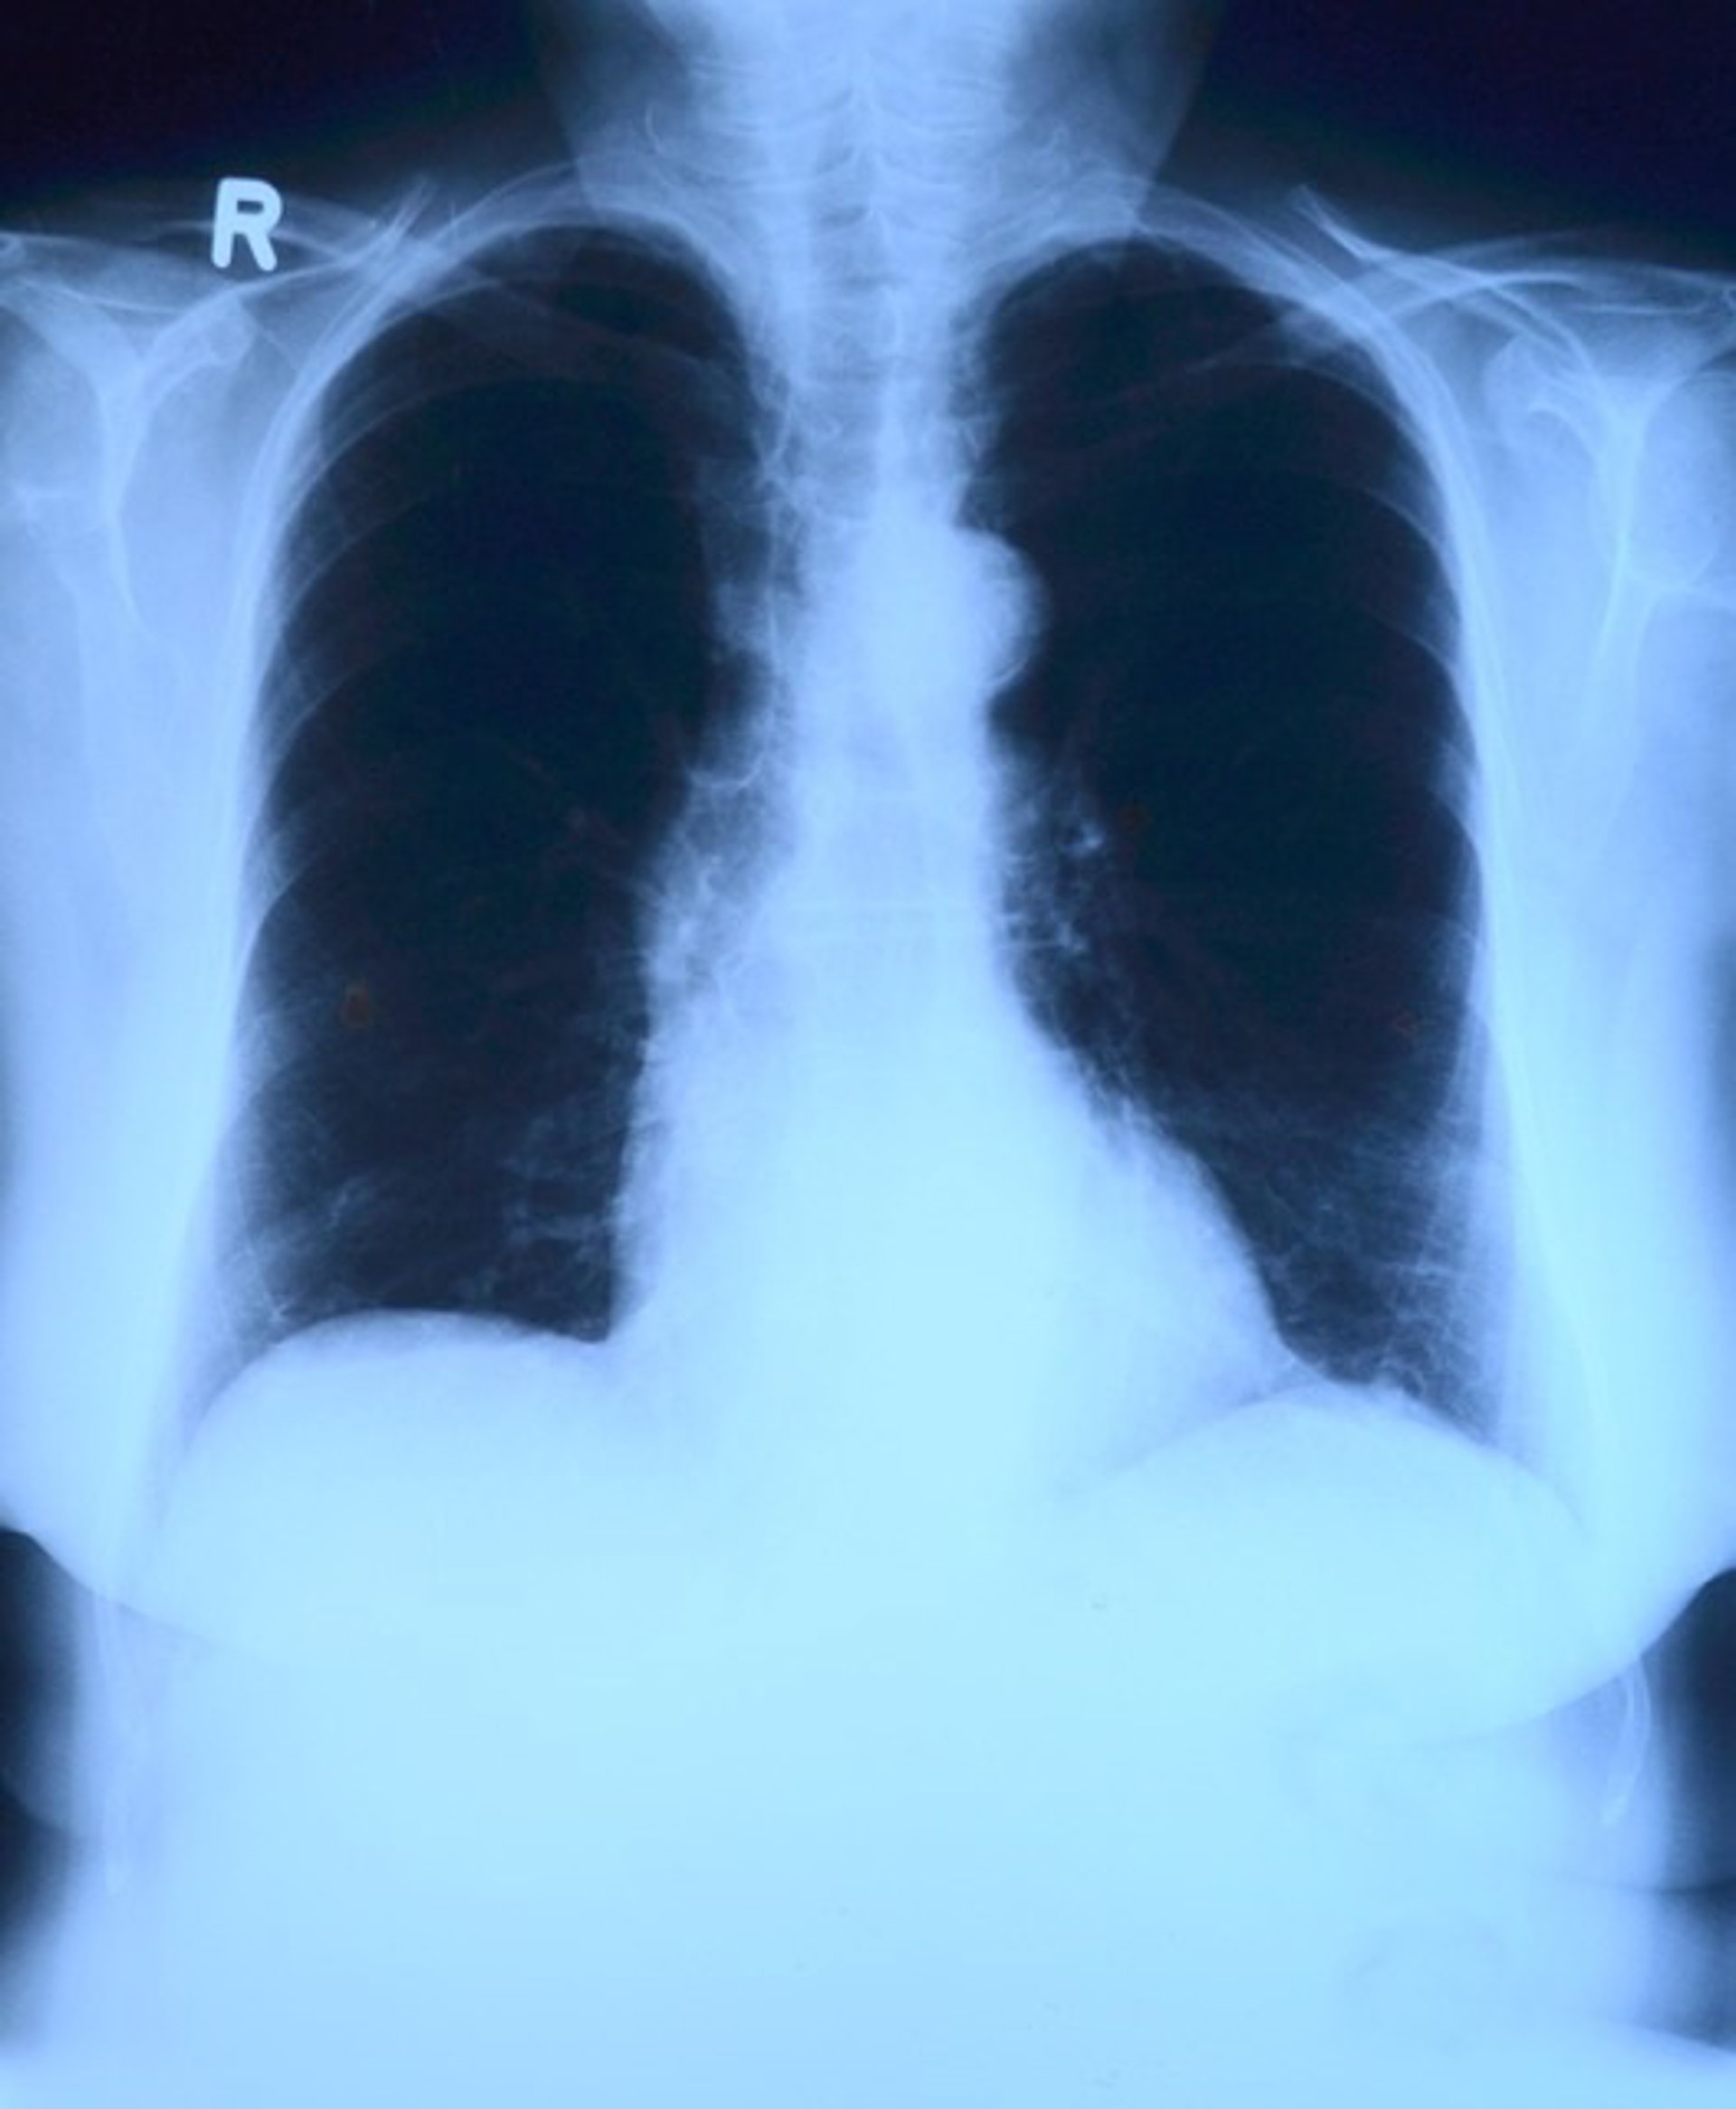

Pulmones, radiografía

Pulmones, radiografía - PIXABAY - Archivo